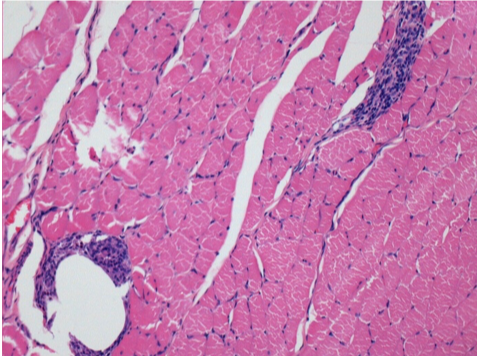

Controllo

Dopo iniezione di NaCl 0.5%

Commento : Niente da dichiarare dopo iniezione di soluzione fisiologica salina.

Sx:Pretibiale-Non trattato

Dx:Pretibiale-Dopo 0.1 ml NaCl 0.9% IM